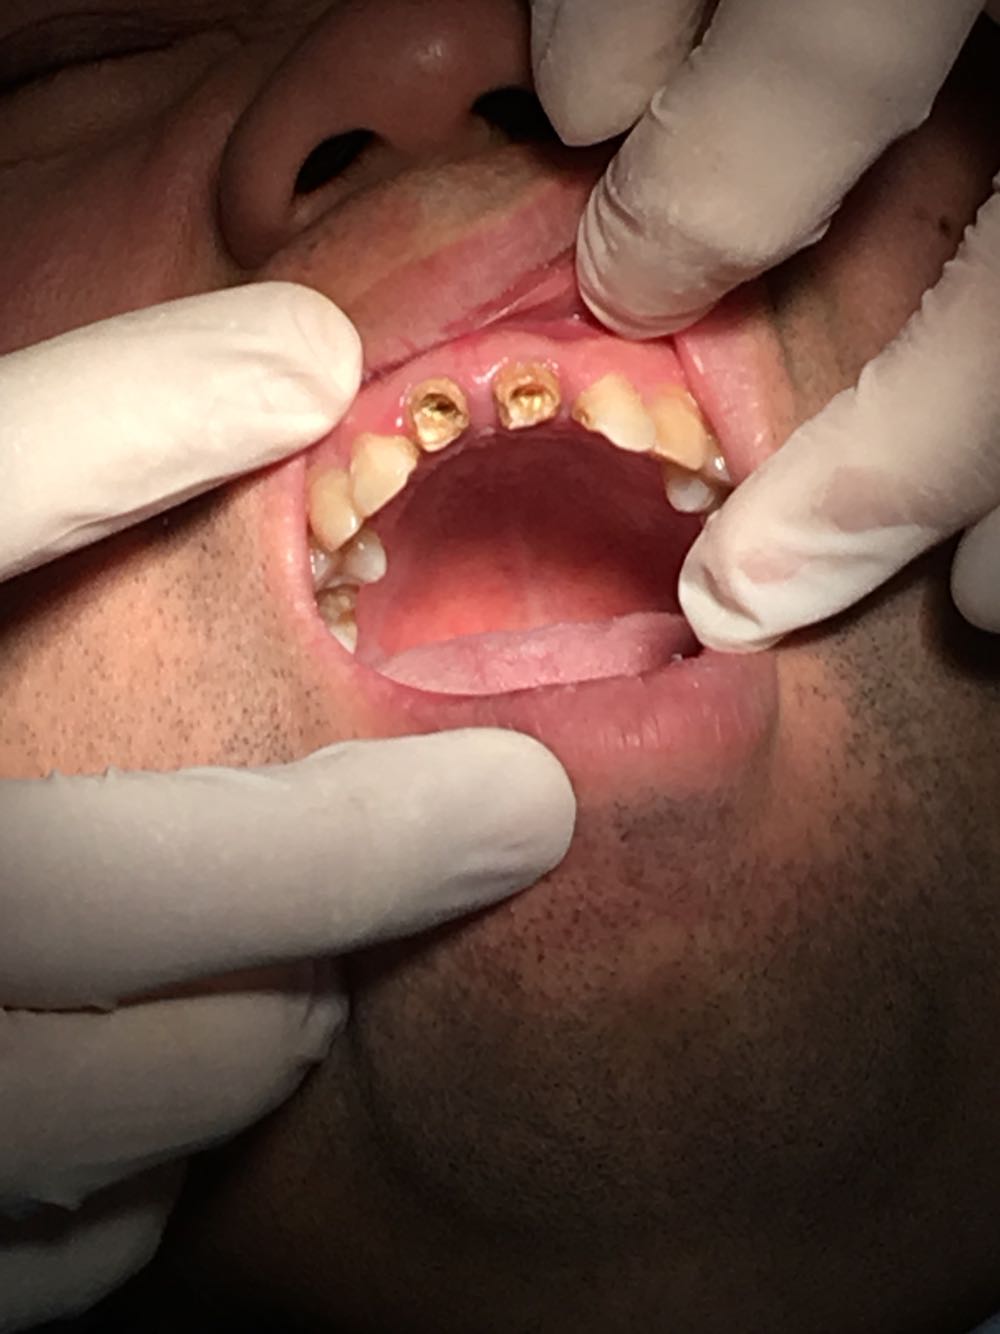

患者:男,41岁,上前牙假牙脱落1天

查:11,21残根无松动,根管内空虚。既往曾镶桩冠牙十多年。X线片示未做根管治疗,11根内可见约3毫米充填物。

11.21残根;治疗方案拟行根管治疗后桩冠修复